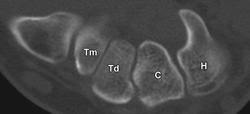

Normal anatomy of the carpal bones. Diagram of the wrist (frontal view) shows the eight carpal bones and the three carpal arcs (Gilula arcs), which are shown as pink (arc I), blue (arc II), and red (arc III) lines. C = capitate, H = hamate, L = lunate, P = pisiform, S = scaphoid, Tm = trapezium, Td = trapezoid, Tr = triquetrum.